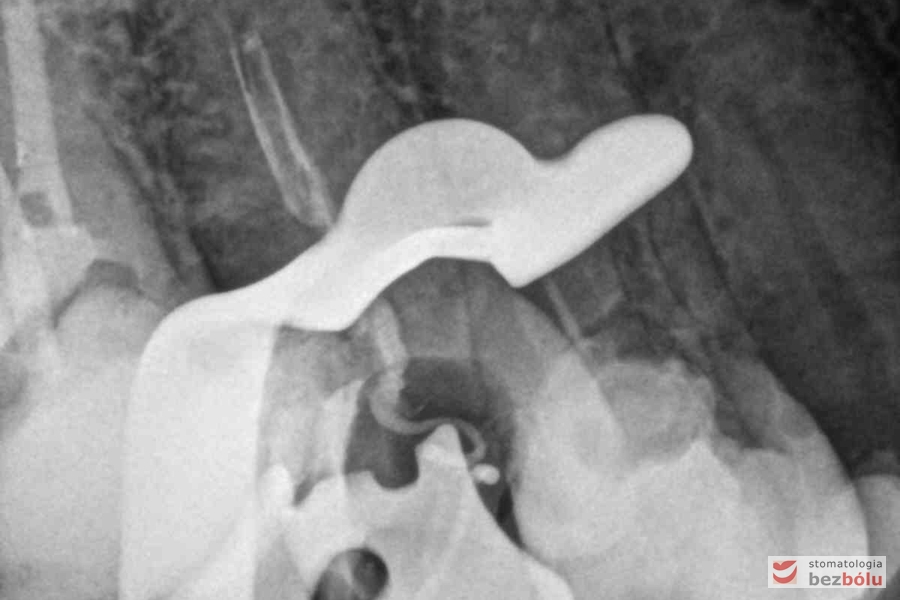

Radiowizjografia - jedynka górna prawa z niedopełnionym kanałem korzeniowym

Radiowizjografia – jedynka górna prawa z niedopełnionym kanałem korzeniowym